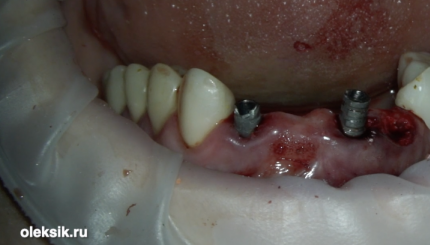

МОСТОВИДНЫЙ ПРОТЕЗ 12-22. НЕМЕДЛЕННАЯ